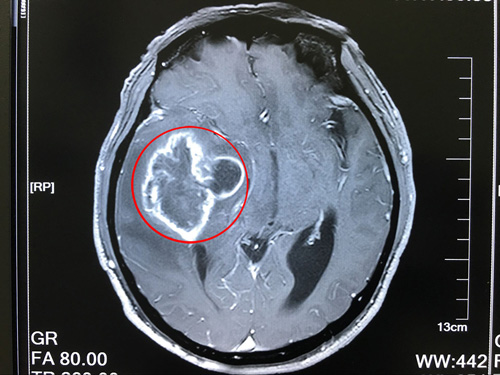

1、頭顱MRI:低度惡性腫瘤呈長(zhǎng)T1長(zhǎng)T2信號(hào),邊界清楚,高度惡性腫瘤顯示更長(zhǎng)T1及T2。少突膠質(zhì)細(xì)胞瘤則顯示瘤體邊界清楚,幾乎無(wú)腦水腫,但不能顯示鈣化。

6、頭顱CT:星形細(xì)胞瘤多為低密度影,腦室內(nèi)腫瘤多為高密度影,多形性膠質(zhì)母細(xì)胞瘤多為混雜密度影。注射造影劑后強(qiáng)化掃描定位準(zhǔn)確率100%,定性達(dá)90%。